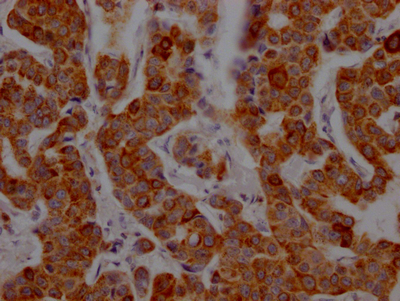

IHC image of CSB-RA934881A0HU diluted at 1:100 and staining in paraffin-embedded human breast cancer performed on a Leica BondTM system. After dewaxing and hydration, antigen retrieval was mediated by high pressure in a citrate buffer (pH 6.0). Section was blocked with 10% normal goat serum 30min at RT. Then primary antibody (1% BSA) was incubated at 4℃ overnight. The primary is detected by a Goat anti-rabbit IgG polymer labeled by HRP and visualized using 0.05% DAB.